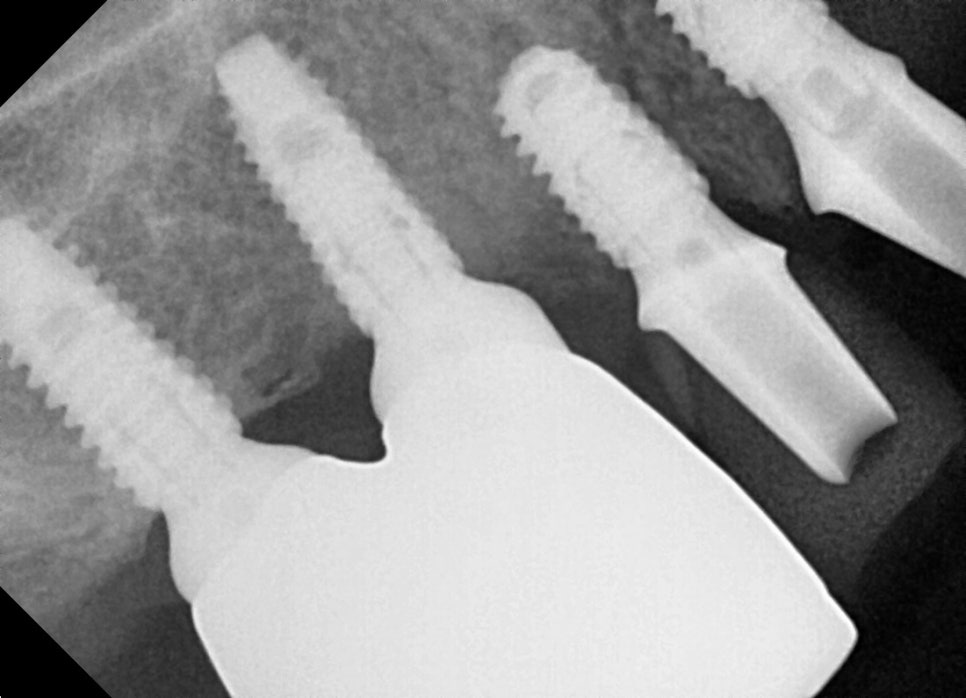

발치 + 임플란트 식립, 한 번에 진행

서울오브치과병원 임플란트

오래된 보철물과 약해진 치아들을 발치한 뒤,

필요한 부위에 임플란트를 바로 심었습니다.

뼈가 부족한 부위는 GBR로 보완해 안정적으로 지지할 수 있도록 했습니다.

상악·하악 임플란트의 각도는 CT 기반으로

미리 계획한 위치에 정확히 식립했습니다.